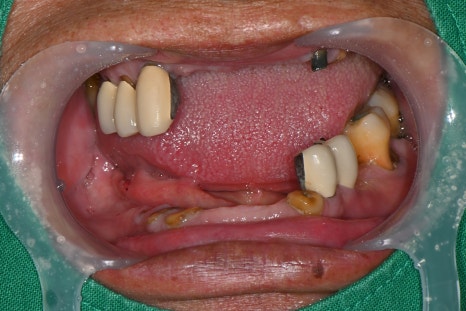

하악 보험 임플란트 식립 후 의 모습

한달 후 상악 전체 발치 진행한 모습